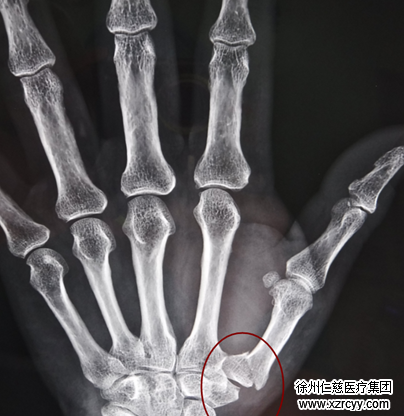

术前检查

Bennett骨折,整复容易固定难

“这是第1掌骨基底部的骨折合并第1腕掌关节的脱位。”接诊的betway在线登陆手外二病区齐伟亚主任,结合摄片及检查情况,对李阿姨的伤情做出准确判定。

第1掌骨基底部骨折脱位又称Bennett骨折,是一种极不稳定的骨折,发生在第1掌骨基底部的骨折合并第1腕掌关节的脱位或半脱位,由爱尔兰外科医生Bennett于1882年第一次描述,是一种涉及关节面的关节内骨折,属于手部的常见骨折。

解释完拗口的医学名词后,齐主任重新拿起片子,指着对李阿姨受伤部位说,因为这个位置的特殊性,整复容易固定较难,若处理不当,会导致拇指活动受限、力量减弱,骨关节退行性变。手部功能的40%-50%由拇指完成,拇指功能障碍将会对患者今后生活带来严重影响。